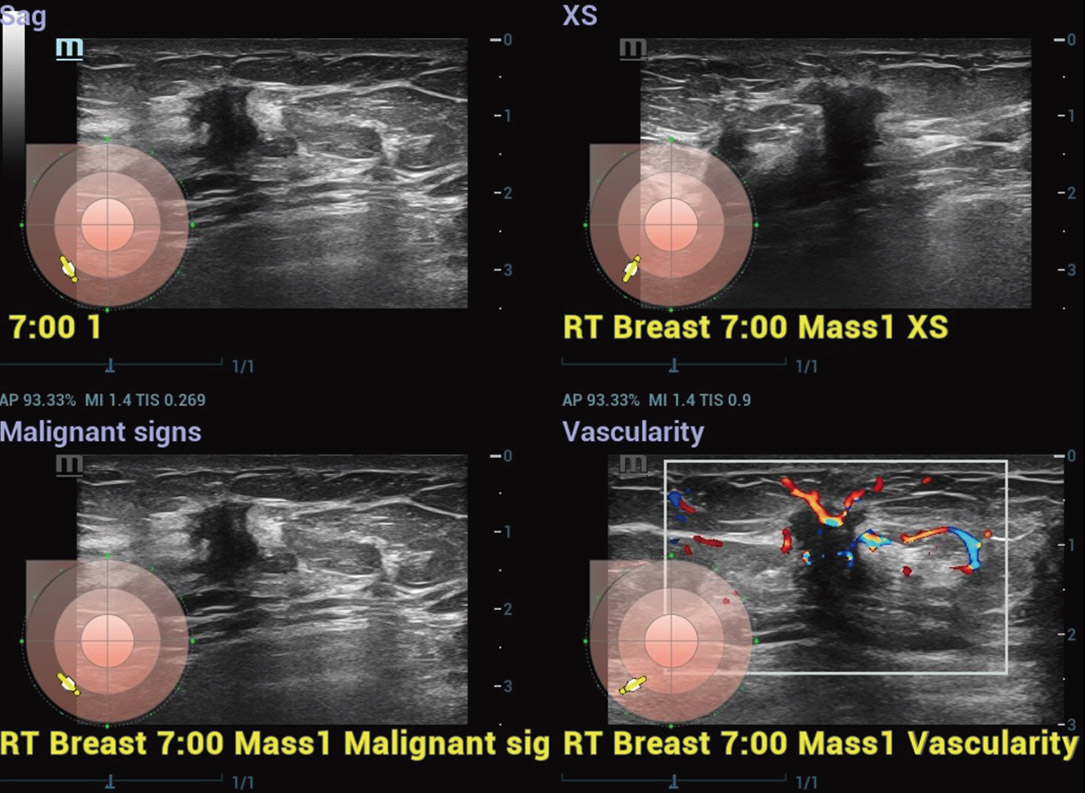

Il cancro al seno Ăš la neoplasia piĂč comune diagnosticata a livello globale. ? la prima causa di morte per cancro nelle donne. La diagnosi precoce del cancro al seno Ăš fondamentale perchĂ© le pazienti allo stadio iniziale hanno una prognosi migliore. In risposta, Resona R9 Platinum Edition offre una soluzione ecografica multiparametrica per il seno che facilita la diagnosi precoce del cancro al seno, la diagnosi e il trattamento accurati del cancro al seno e la ricerca clinica all'avanguardia.

Strumenti di analisi multiparametrica M-Reference

M-Ref. C&E

M-Ref. C&E tumore maligno al seno

M-Ref. C&E supporta la visualizzazione del contrasto e della STE in un unico piano per una valutazione comparativa della perfusione e dell'elasticitĂ .

M-Ref. E Compare

M-Ref. E Compare tumore maligno al seno

M-Ref. E Compare supporta la visualizzazione dell'elastografia strain in tempo reale e della STE in un unico piano per la valutazione della rigiditĂ dei tessuti.

Smart Breast

Smart Breast Ăš uno strumento di analisi e refertazione delle ecografie mammarie che rende la routine clinica delle ecografie mammarie piĂč accurata e produttiva. La gestione sistematica delle lesioni multiple e la valutazione a quattro piani garantiscono ulteriori informazioni diagnostiche. Inoltre, il flusso di lavoro automatizzato semplificato fornisce una scansione del seno piĂč efficace.

Elastografia Strain

- SensibilitĂ , produttivitĂ , penetrazione e precisione elevate

- Un unico "involucro" per l'analisi dell'area di infiltrazione del tumore

Elastografia Strain